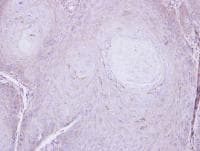

Rabbit Polyclonal C16orf62 antibody. Suitable for WB, IHC-P and reacts with Human samples. Cited in 2 publications. Immunogen corresponding to Recombinant Fragment Protein within Human VPS35L aa 1-150.

Applications IHC-P, WB